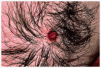

Se trata de un hombre de 26 años de edad que consultó por una lesión localizada en su axila izquierda, que no producía ningún síntoma salvo la molestia inducida por el roce, de unos 8 meses de evolución. En la exploración dermatológica se observó una tumoración eritematosa, excrecente, blanda, bien delimitada y que asentaba sobre una piel de aspecto normal (fig. 1). La lesión fue extirpada quirúrgicamente y sometida a estudio dermatopatológico. Se observó un tumor bien delimitado, con un collarete epidérmico, compuesto por múltiples estructuras tubulares, algunas de las cuales se encontraban aisladas en el seno del tumor, pero otras estaban en relación con invaginaciones epidérmicas en una zona de la lesión (fig. 2). Los túbulos se encontraban embebidos en un estroma marcadamente fibroso y tenían un diámetro muy variable, llegando a adoptar los más dilatados un aspecto quístico (fig. 3). A mayor detalle se observaba que la pared de los túbulos estaba compuesta al menos por dos capas celulares (la externa de morfología cúbica y la interna columnar); en la luz tubular existían proyecciones papilares intraluminales y secreción por decapitación y el estroma tumoral presentaba un rico infiltrado de linfocitos y células plasmáticas (figs. 4 y 5). Este cuadro clinicopatológico fue diagnosticado como ATA, aunque focalmente las imágenes histopatológicas eran indistinguibles de las de un SCAP.

Fig. 1.--Imagen clínica de la lesión.